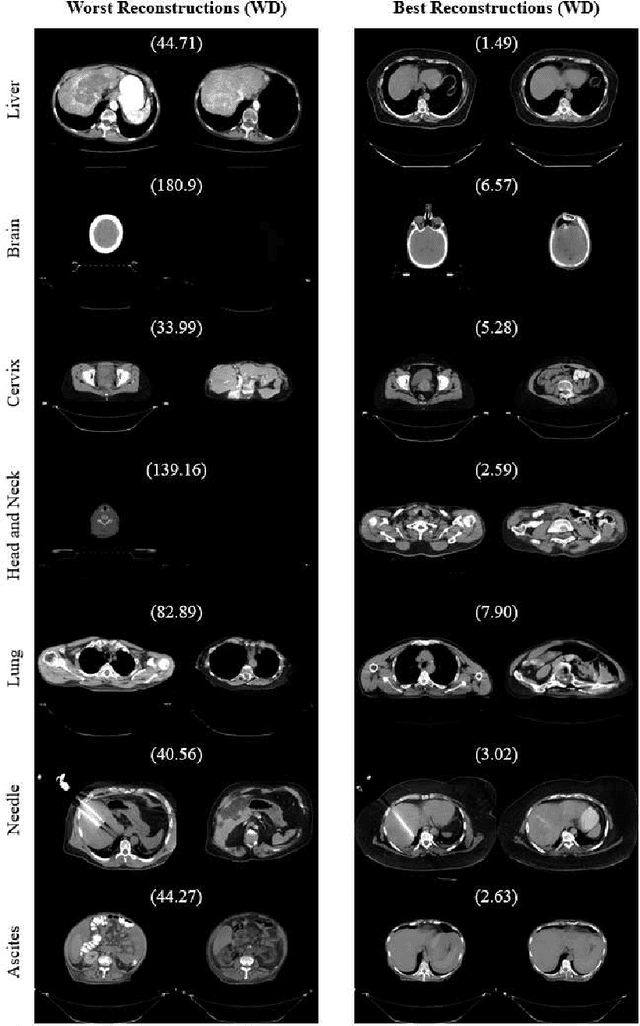

Abstract:One barrier to the clinical deployment of deep learning-based models is the presence of images at runtime that lie far outside the training distribution of a given model. We aim to detect these out-of-distribution (OOD) images with a generative adversarial network (GAN). Our training dataset was comprised of 3,234 liver-containing computed tomography (CT) scans from 456 patients. Our OOD test data consisted of CT images of the brain, head and neck, lung, cervix, and abnormal livers. A StyleGAN2-ADA architecture was employed to model the training distribution. Images were reconstructed using backpropagation. Reconstructions were evaluated using the Wasserstein distance, mean squared error, and the structural similarity index measure. OOD detection was evaluated with the area under the receiver operating characteristic curve (AUROC). Our paradigm distinguished between liver and non-liver CT with greater than 90% AUROC. It was also completely unable to reconstruct liver artifacts, such as needles and ascites.